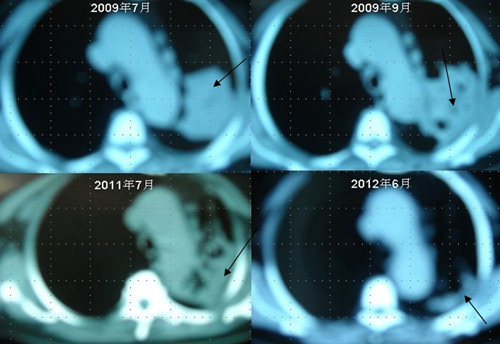

[提要] 患者李某某,女,64歲,于2009年6月因咳嗽、喘憋、痰中帶血,經(jīng)CT及病理等相關(guān)檢查確診為右肺上葉粘液腺癌, 縱膈淋巴結(jié)轉(zhuǎn)移, 左胸膜轉(zhuǎn)移,胸腔積液,因病情及體質(zhì)的原因無法接受手術(shù)及放化療等殺傷性治療,采用"中醫(yī)調(diào)胃、強(qiáng)腎、止血、化巖法"先后共治療8個月,現(xiàn)患者已有質(zhì)量的存活近3年。目前隨訪患者飲食、睡眠、體力均好,可獨(dú)立完成日常家務(wù),如今患者已經(jīng)67歲。肺癌病人李XX的病理圖片肺癌病人李XX采用“董氏治癌法”治療前后CT變化

肺癌病人李XX采用“董氏治癌法”治療前后CT變化